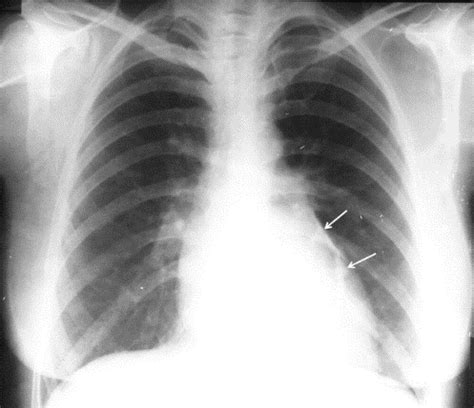

Când un nou-născut prezintă simptome sugestive pentru pneumotorax, echipa medicală acționează rapid pentru a confirma diagnosticul și a stabiliza starea copilului. Metoda standard de confirmare este radiografia toracică. Această imagine permite medicilor să vizualizeze clar prezența aerului în spațiul pleural - apare ca o zonă întunecată, fără structură pulmonară.